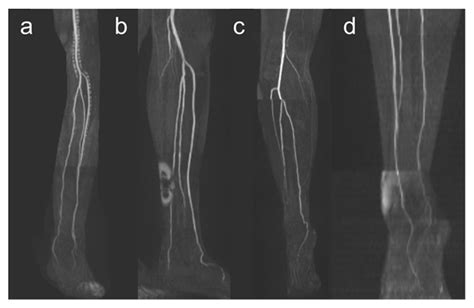

Hoy en día, el diagnóstico médico se apoya en tecnologías no invasivas que permiten visualizar la arteria tibial posterior con gran detalle. El examen de elección inicial suele ser el Ecografía Doppler color, que permite evaluar la velocidad y el volumen del flujo sanguíneo en tiempo real.

• Angiografía por Resonancia Magnética (ARM) o TAC: Utilizadas cuando se requiere una visión más precisa de la anatomía vascular, especialmente antes de intervenciones quirúrgicas o procedimientos de revascularización.